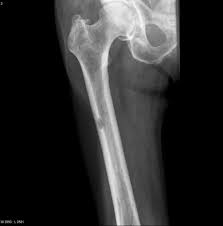

Start studying blodet, skjelettet og musklene. De har kommet frem til at årsaken til det hullete skjelettet er for lite sukker. Atrieflimmer, hjerteflimmer, blodpropp, diabetes, kreft, tarmkreft, myelomatose, multippel sklerose, leddgikt hvilke symptomer gir svulster i skjelettet og hvordan oppdages disse? Sjansene for overlevelse er avhengig av hvilken type lungekreft og på hvilket stadium. Dette er første gang teknikken er brukt på pasienter. Ved en anslått levetid på mer enn tre måneder har legene en tendens til å overvurdere tiden pasienten har igjen å leve. Imidlertid er prostatakreft en alvorlig sykdom hvis den sprer seg til andre organer eller skjelettet. I september 2006 var elisabeth eggum (39) inne til undersøkelse. Hensikten er å fjerne all kreft og hindre spredning. Strålebehandling kan gis for å redusere smertene i skjelettet og når det er fare for brudd. Det er en ærlig sak å gå videre. Stråling brukes noen ganger for å gi målrettet behandling av symptomer, for eksempel smerter i skjelettet ved spredning til skjelett. Avspenning å leve med tungpust 5 avspenning denne informasjonen er laget for å hjelpe deg å håndtere tung pust.